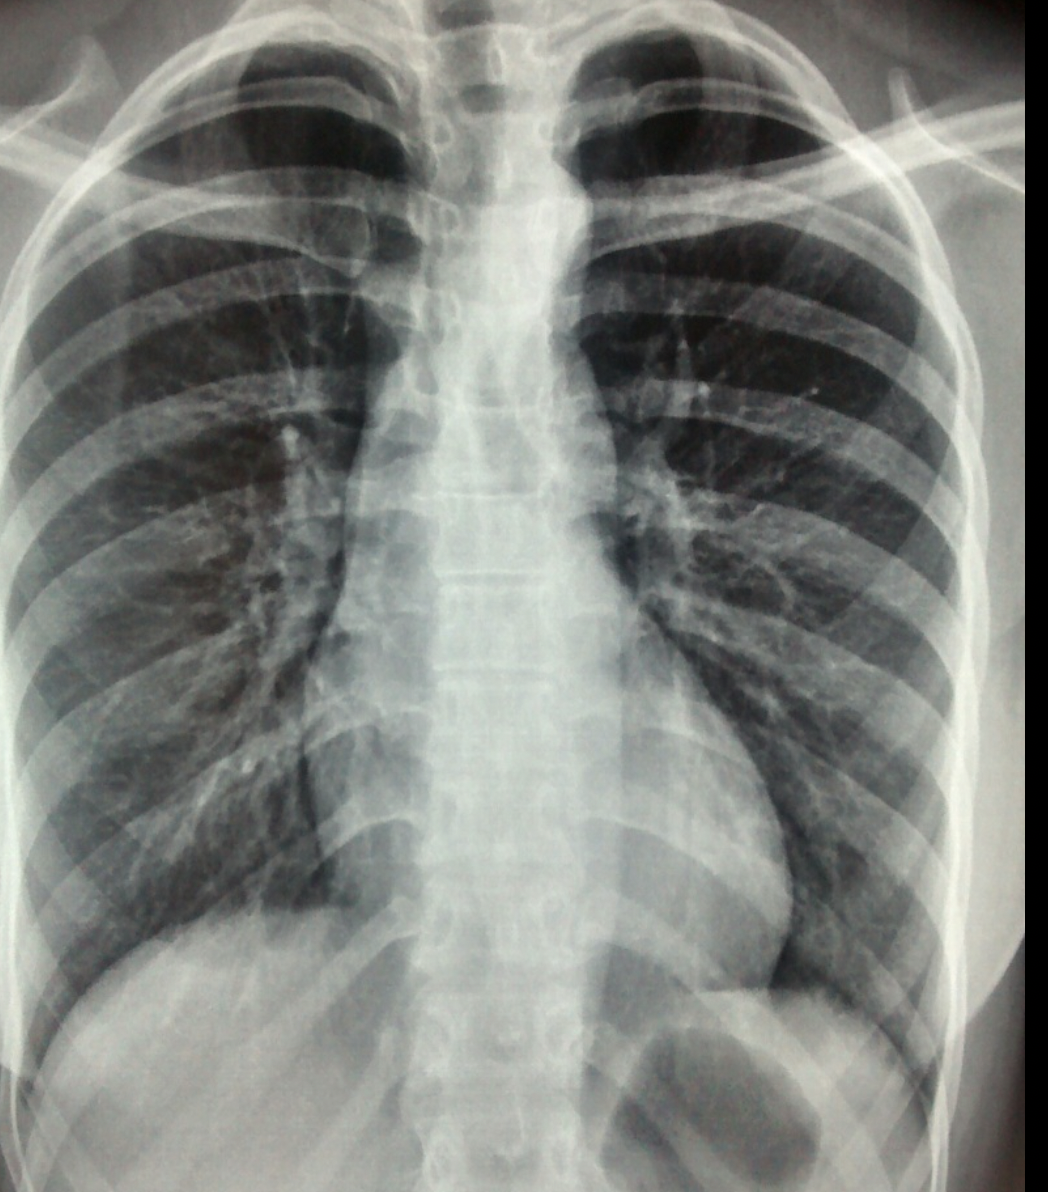

30

-Mitral valve replacement -Left atrial enlargement (Splaying carina, double right sided border sign) -Cardiomegaly